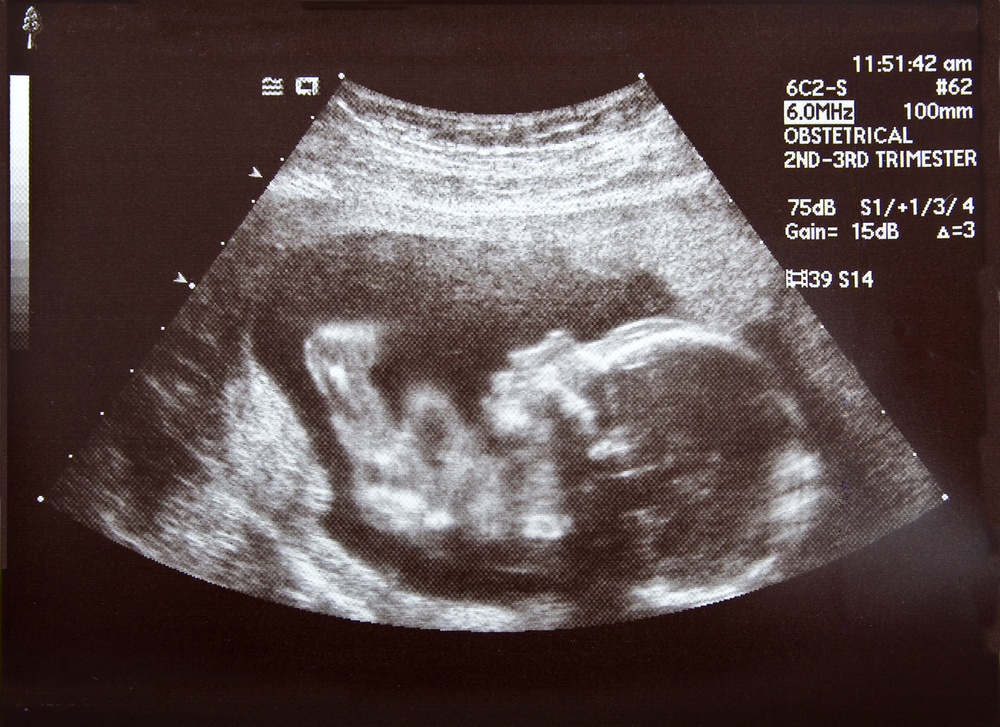

As Brittani has progressed in her pregnancy, Madilyn keeps getting bigger while Mason's growth has slowed. But this past Tuesday, doctors captured something magical during her weekly ultrasound.

"We didn't really see much, (the doctor) said there's his hand and there's her hand and it looks like they're holding hands," Brittani told KWCH. "Most twins, when (the doctor's) trying to take pictures and stuff, they're kicking each other and hitting each other, and she said with our twins it seems like she was very protective over him."